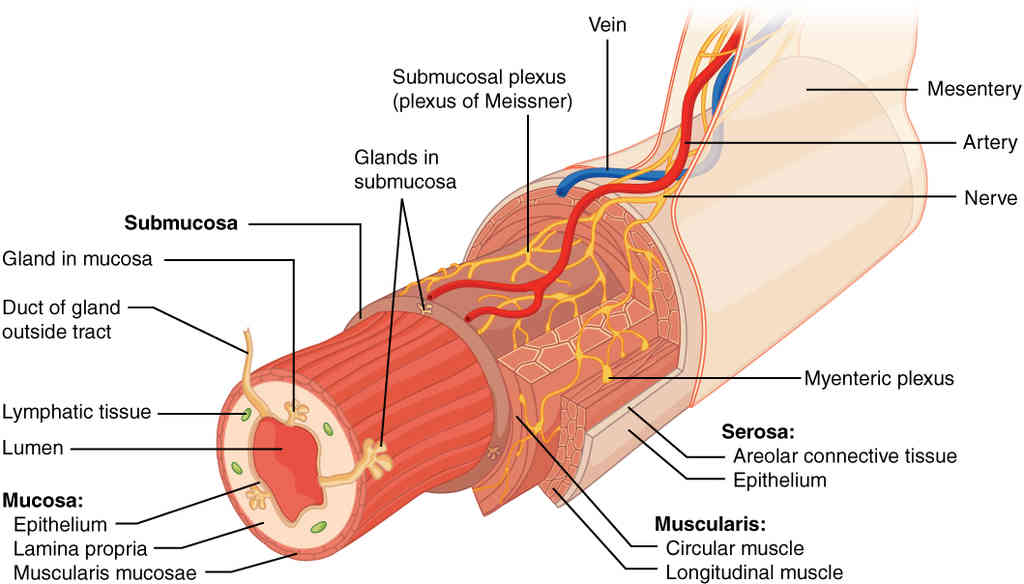

This page is under construction. For now, it is just a resource of the images found in the OpenStax Anatomy and Physiology Handbook. It wil slowly change into a revision tool. Each slide has a number. Use this to refer to the slide. When completed, it will have an unlabelled section, with labelled slides in parallel. On the unlabelled slides, write your answer and use the labelled slide to assess yourself. Keep track by also noting the number on each slide. Improvement at each attempt is important, more so than full marks on a first attempt.